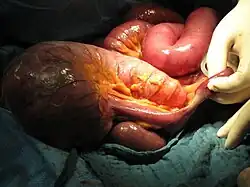

Bleibt der Ileus unbekannt, kann es zu einer Perforation der Darmwand kommen. Dies bedingt eine kotige Peritonitis.

Behandlung

Die Therapie richtet sich nach der zugrundeliegenden Ursache. Das gilt auch bei eventueller Operation für das anzuwendende Verfahren. Handelt es sich um einen paralytischen Ileus, kann mittels Prokinetika die Darmaktivität angeregt werden. Liegt ein mechanischer Ileus,[6] etwa durch eine Strangulation oder eine Bride, vor, ist eine zügige operative Intervention, mittels Laparotomie[7] oder heute bevorzugt mittels minimalinvasiver Technik (Laparoskopie), indiziert.